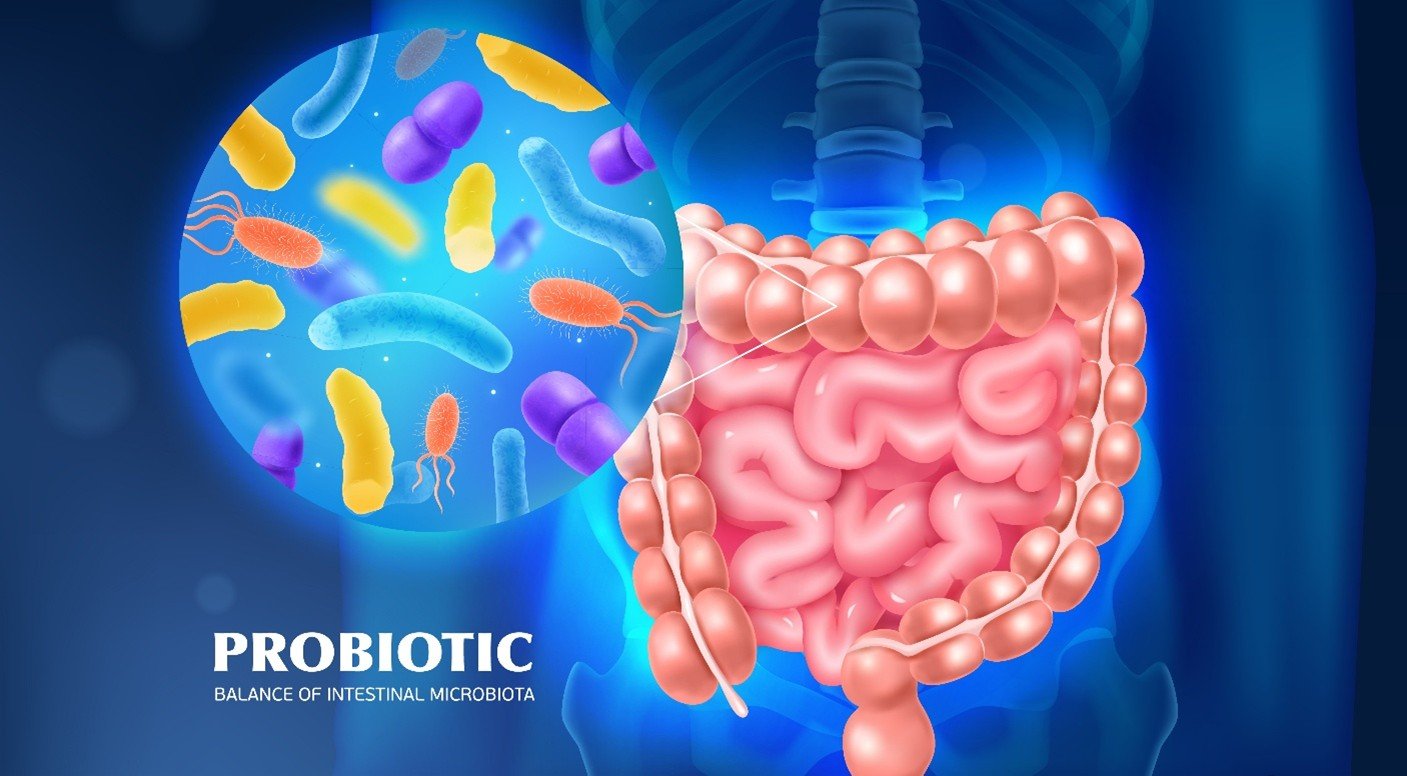

- Oral Microbiome: The ecosystem of microorganisms in the mouth plays a role in oral health. Body shifts of this balance can result in dental caries (cavities) and gum diseases like gingivitis and periodontitis.

- Periodontal Disease and Systemic Effects: Periodontal disease, which is a bacterial infection in the dental plaque, causes inflammation and degradation of gum tissue and bone, which support the teeth. Infections and inflammation of gums may transiently enter the bloodstream (transient bacteremia), distributing bacteria, microbial toxins, and inflammatory mediators to the body.

- Mechanisms of Influence: Mechanisms through which oral infections may have systemic consequences include the translocation of bacteria throughout the body, transmission of bacterial toxins, and systemic inflammation initiated by oral bacteria. These can aggravate chronic inflammation and immune responses that lead to systemic illnesses.